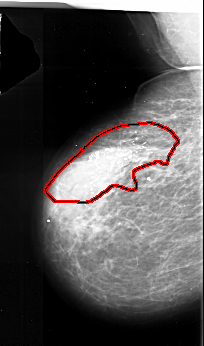

FILE: A_1017_1.LEFT_MLO.OVERLAY

TOTAL_ABNORMALITIES 1

ABNORMALITY 1

LESION_TYPE CALCIFICATION TYPE PLEOMORPHIC DISTRIBUTION SEGMENTAL

ASSESSMENT 5

SUBTLETY 5

PATHOLOGY MALIGNANT

TOTAL_OUTLINES 1

BOUNDARY

LEFT_CC LINES 5221 PIXELS_PER_LINE 3586 BITS_PER_PIXEL 16 RESOLUTION 42 OVERLAY